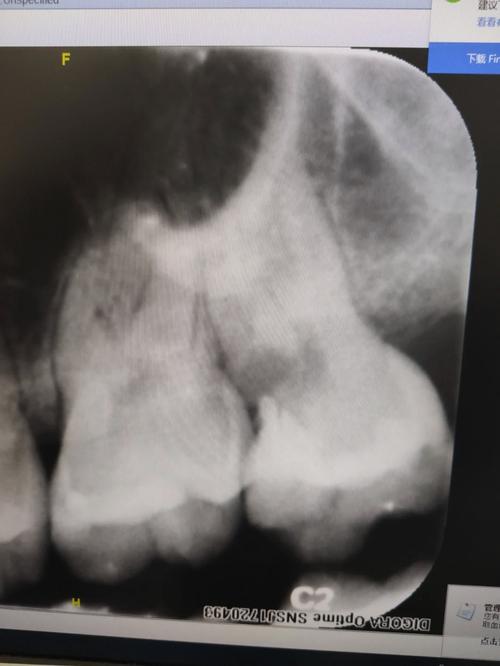

急性牙髓炎主要是由于牙髓因细菌感染而发生急性炎症,细菌产生毒素,使封闭的牙髓腔内的压力急剧增高,同时压迫牙髓产生剧烈疼痛急性牙髓炎的疼痛具有一定的特点,一般表现为夜间痛、自发性放射性疼痛,冷热刺激痛,患者不能定位,检查时牙冠表面常可见龋洞。患者急诊就诊时可予以开髓减压,疼痛可立即缓解,...。